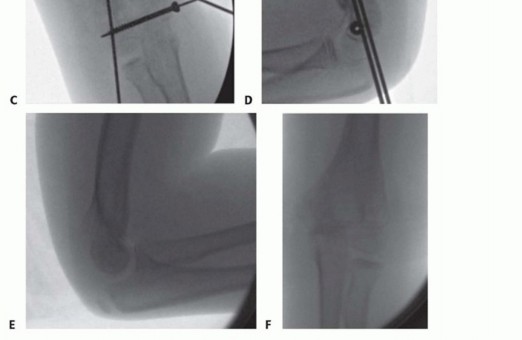

T-condylar fractures of the distal humerus in children and adolescents are relatively rare occurrences. They are thought to represent 2% of all pediatric elbow fractures.5The proposed mechanism is similar to that of pediatric supracondylar fractures but with a higher energy mechanism of injury.6 FIG 1 • A,B. An 8-year-old boy with T-condylar distal humerus fracture. C,D. Fixed with mini-open reduction with intercondylar screw compression and K-wire fixation of the distal humerus to the shaft. E,F. After hardware removal, the patient had 0 to 140 degrees range of motion with no pain.